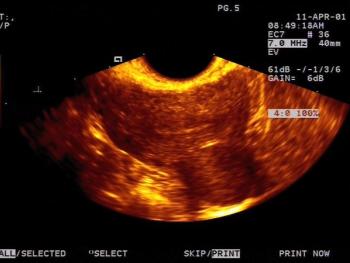

This is a confirmed case of scar ectopic pregnancy. Yesterday, I carried out this exam in an emergency room, without much time to perform an adequate sonogram, the patient did not feel good with “cramps” but no signs of bleeding.

Implantation in the scar of a previous Cesarean is thought to be the rarest of ectopic pregnancies. With the increasing numbers of Cesareans performed, scar implantation may become more frequent as well. We present an illustrative case.